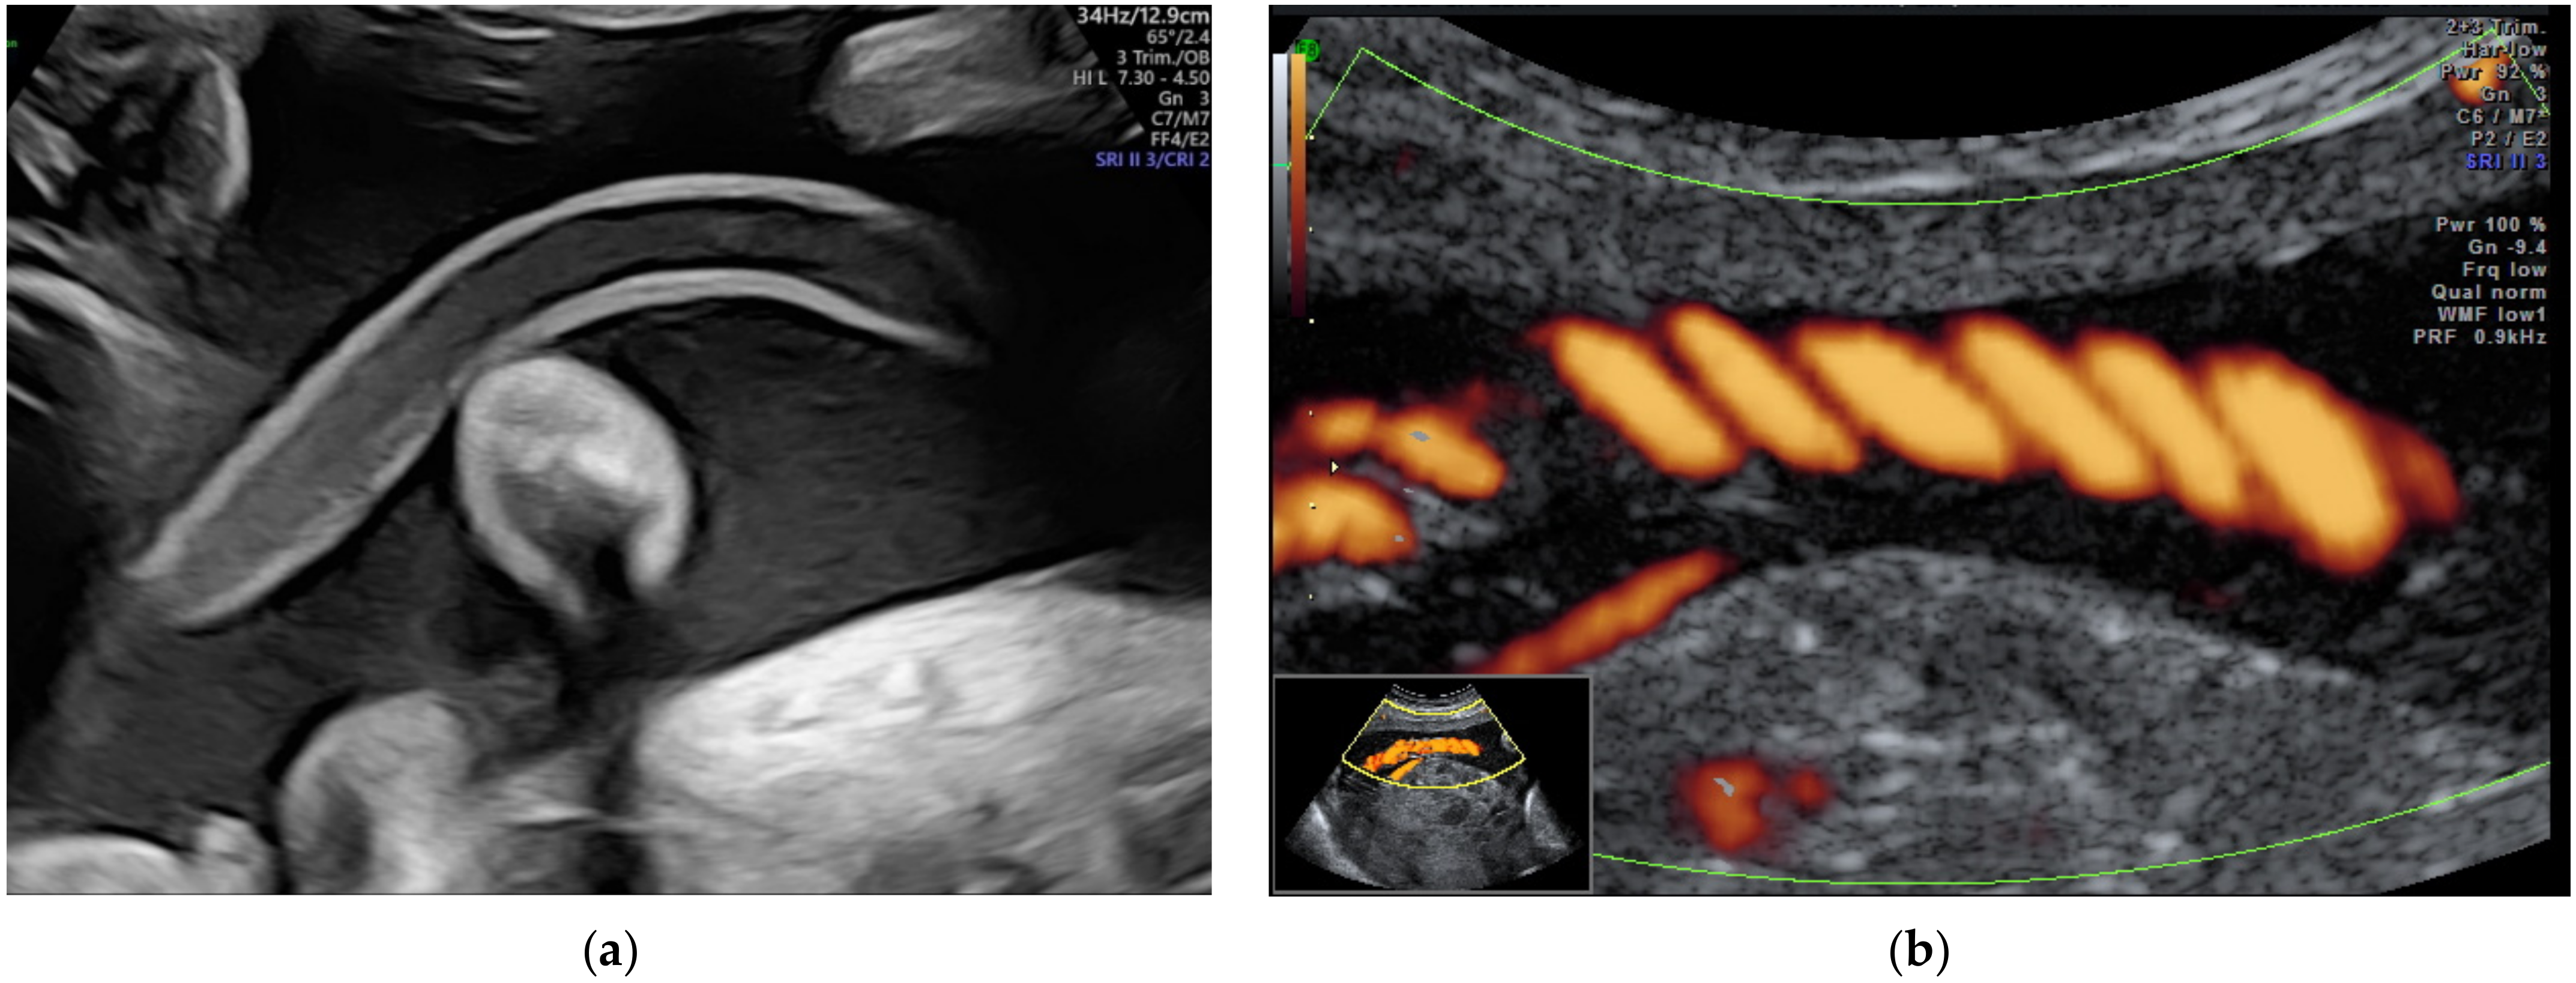

2.8. Cord Knots